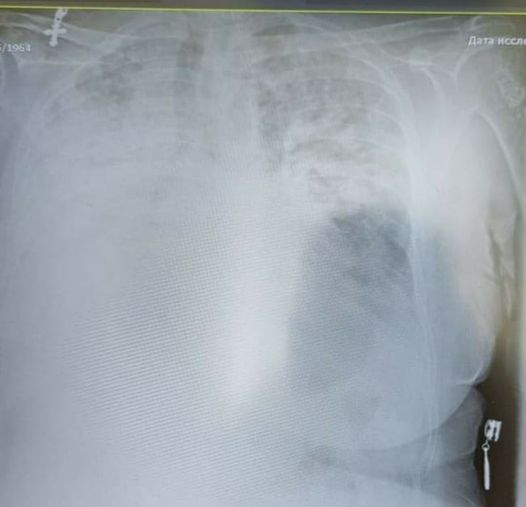

На фото легені коронавірусного хворого!”